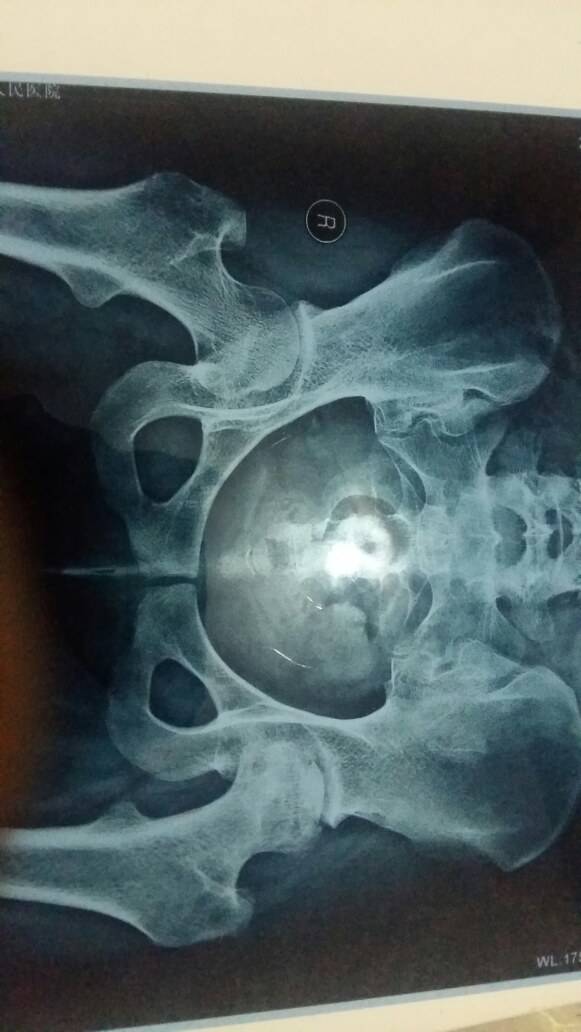

我都已经两边都不对称了, 明显塌陷。

左侧股骨头坏死塌陷了

左腿比较严重,可以值骨,但是千万别钻孔减压,会加速塌陷。